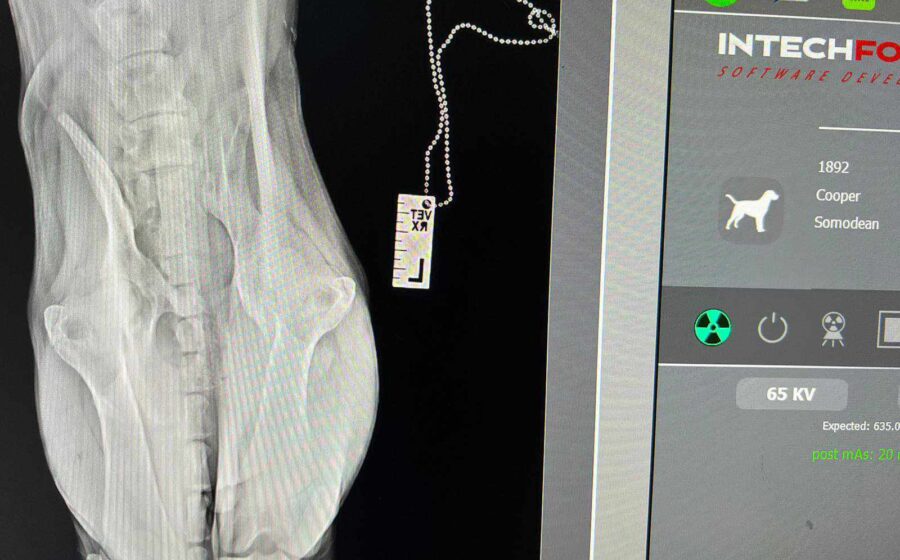

Sommersprosse stand seit seiner Geburt wacklig auf seinen Hinterbeinen. Sein 92-jähriger Besitzer, der Sommersprosse ausschließlich im Haus hielt, weigerte sich jedoch, den Welpen untersuchen zu lassen. Um die Wachstumsentwicklung von Sommersprosse zu unterstützen, ging unsere Tierschützerin Tina regelmäßig vorbei und brachte Futter, Vitamine, Mineralien und Ergänzungsmittel mit. Eines Tages beschloss der alte Mann, Sommersprosse nach draußen zu lassen, wo er prompt von einem Auto angefahren wurde. Daraufhin hat Tina Sommersprosse zu sich in Pflege genommen und ihn direkt untersuchen lassen. Auf den Röntgenbildern wurden angeborene Schäden der Wirbelsäule und Hinterläufe, sowie ein weiterer Wirbelsäulenschaden durch den Unfall festgestellt. Spazierte Sommersprosse anfangs noch auf wackligen Hinterbeinen durchs Leben, hat sich seine Gehbehinderung jetzt deutlich verschlechtert. Auch ist der süße Bub hierdurch größtenteils inkontinent geworden und braucht spezielle Versorgung.

Das bedeutet, dass seine Blase manuell entleert werden muss.